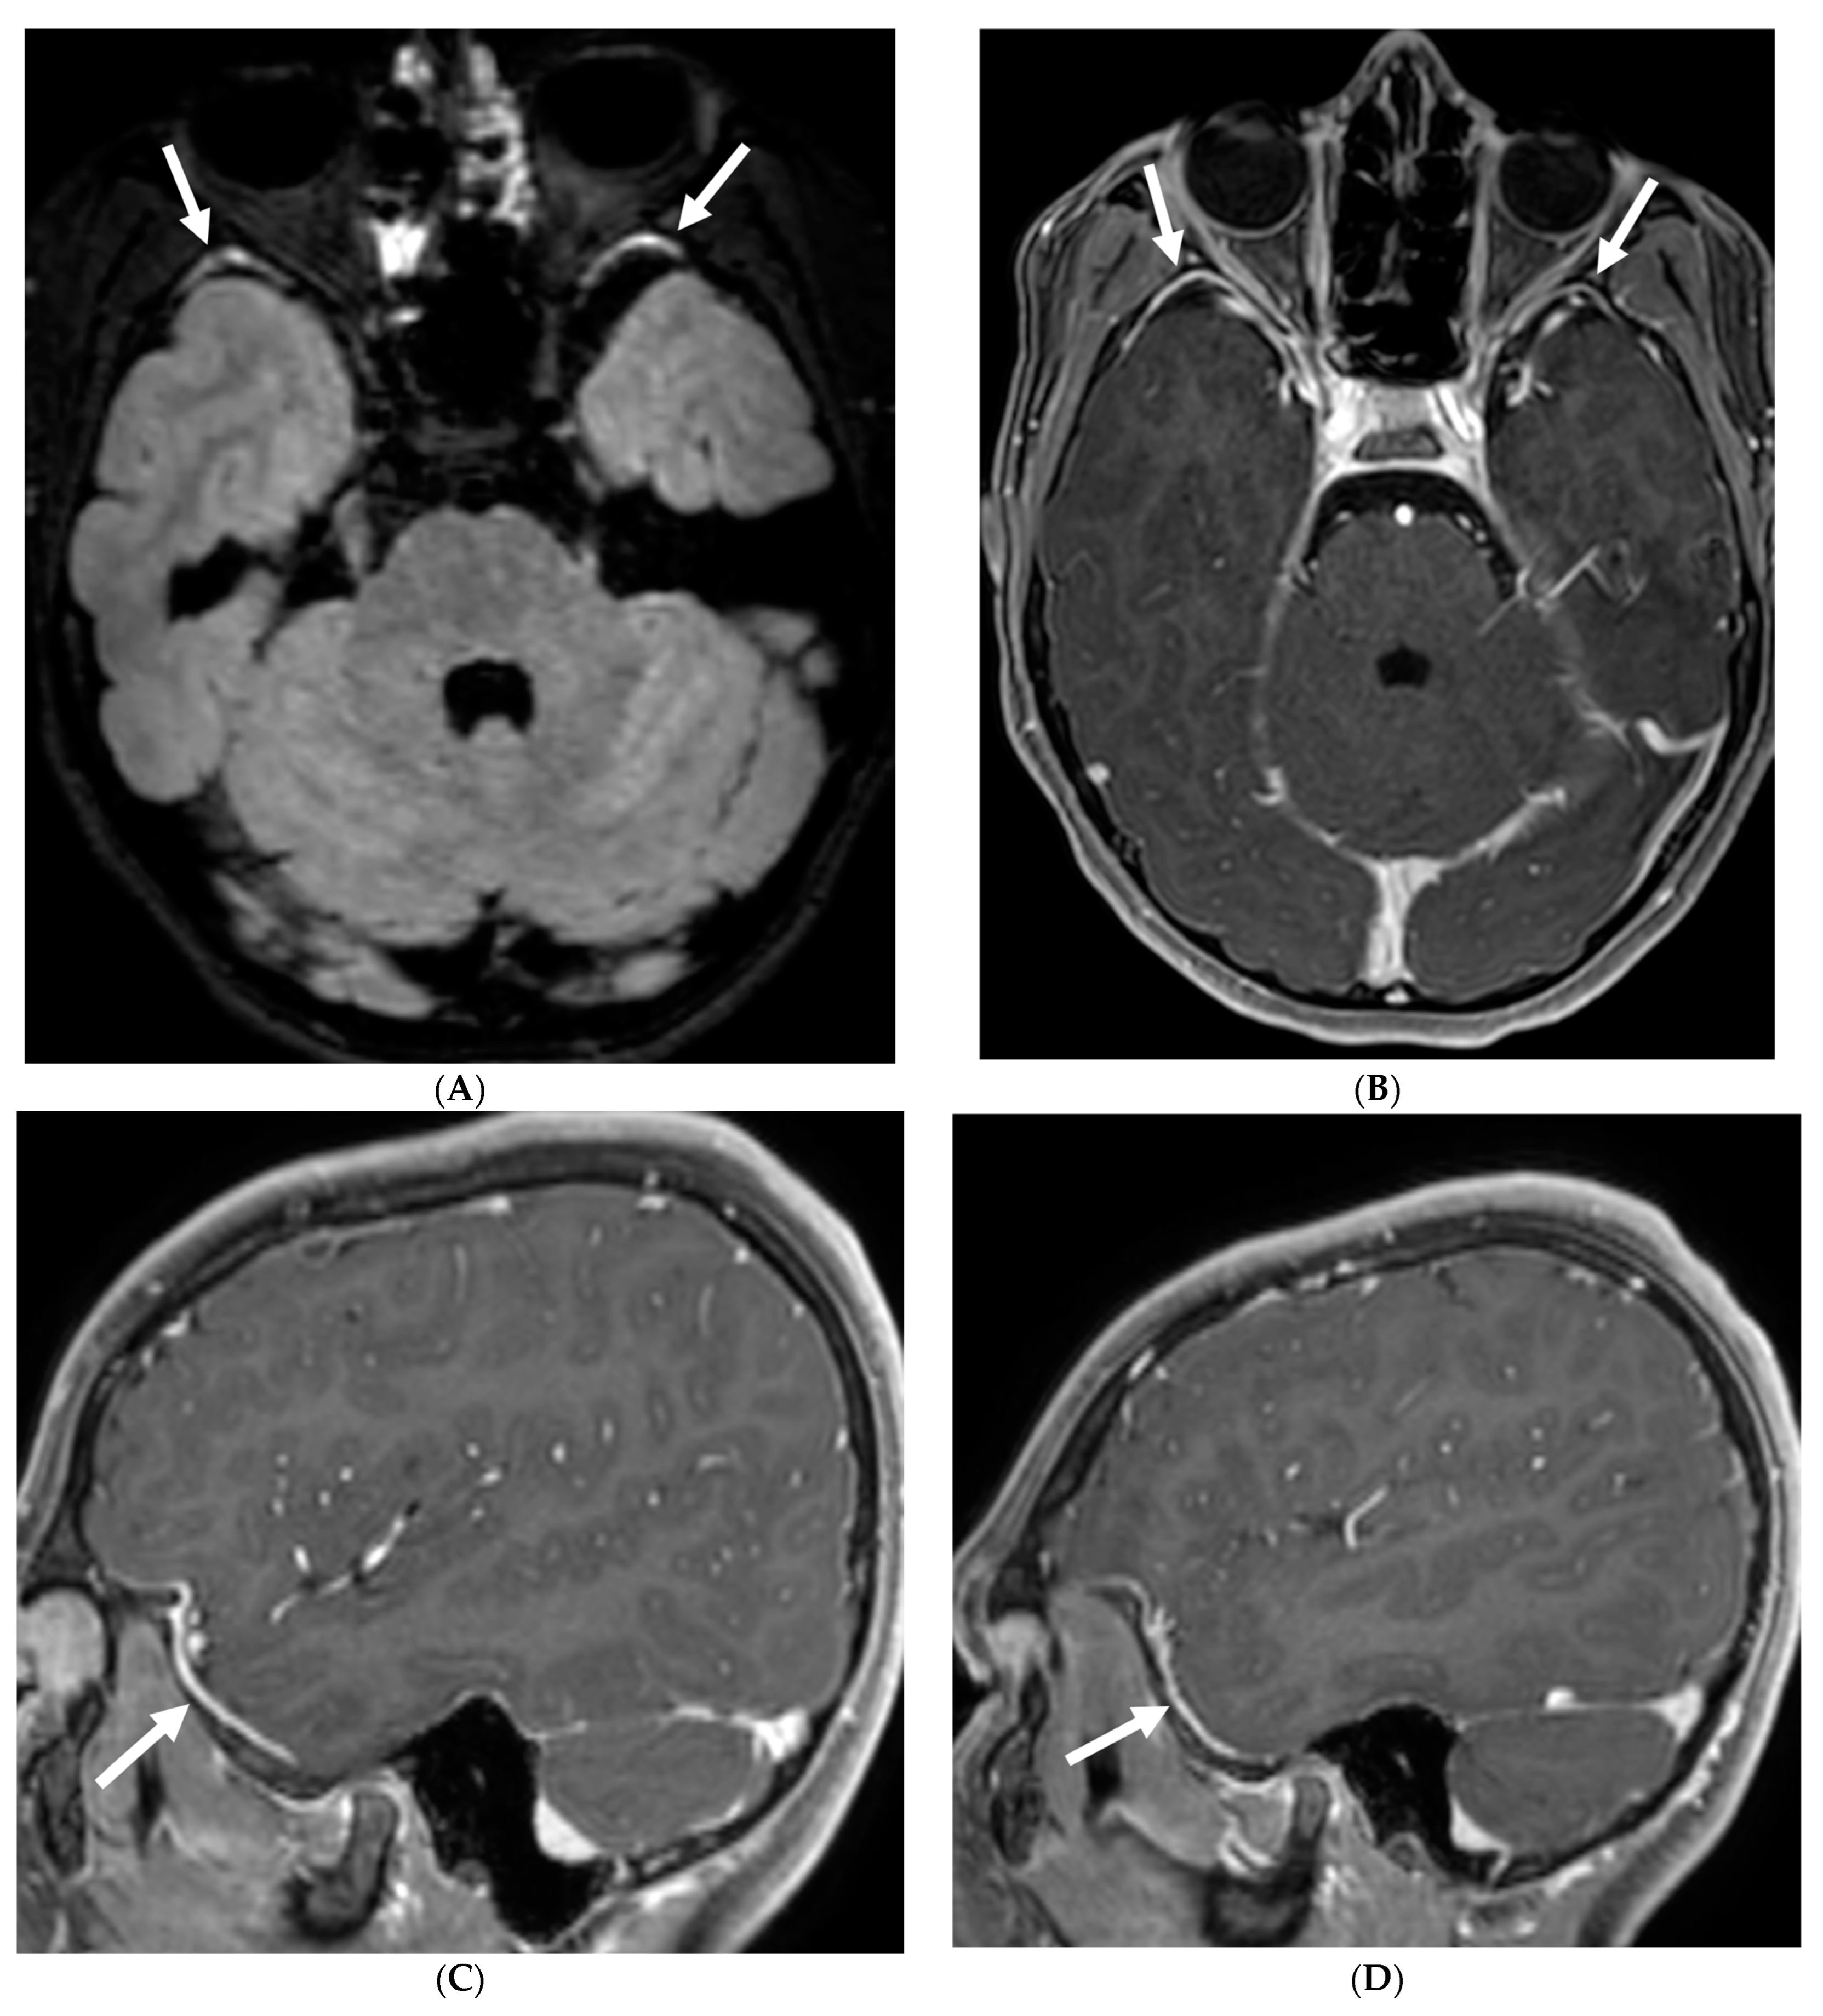

3.6. Glioneuronal Tumor

Diffuse leptomeningeal glioneuronal tumor (DL-GNT) is a recently classified brain tumor (WHO 2016) previously known by various terms such as disseminated oligodendroglial-like leptomeningeal tumor, dysembryoplastic neuroepithelial tumor-like neoplasm and meningeal gliomatosis [52]. It is also associated with precancerous conditions such as KIAA1549-BRAF gene fusion, 1p deletion or 1p/19q co-deletion and Haberland syndrome [53,54].

Although a low-grade neoplasm, leptomeningeal spread is the norm [55]. DL-GNT is characterized by diffuse leptomeningeal thickening, often with basal predominant nodular enhancement [56]. There is invariable involvement of the leptomeninges along the spinal cord in linear fashion [57]. Distinctively, numerous small T2-hyperintense parenchymal cysts are present as a result of fibrosis and obstruction in the subarachnoid space; typically in the inferior frontal and medial temporal lobes [53]. These cysts show incomplete signal suppression on T1 and FLAIR images, possibly reflecting their mucoid nature [53,57]. Engulfment of peripheral nerve roots and invasion of choroid plexus may be seen (Figure 6) [55]. The diagnosis of DL-GNT be pursued with characteristic imaging findings with infectious etiology been ruled out [56].

Figure 6.

Axial FLAIR (A), Axial T2 orbits (B), Axial T1 orbits post contrast (C) and axial T1 post contrast (D): 13-year-old female with headache and blurred vision. Abnormal FLAIR hyperintensity involving the left parieto-occipital periventricular white matter (arrow), and bilateral cerebellar hemispheres. Bilateral papilledema (black arrow) and edematous left optic nerve (dashed arrow). Peripheral optic nerves/optic sheath enhancement in the posterior aspect (curved arrows). Demyelination, infectious and metastatic processes were considered. MRI brain 6 months later with persistent symptoms demonstrates patchy and asymmetric pachymeningeal and leptomeningeal enhancement (open arrows). Pathology: Diffuse Leptomeningeal Glioneuronal Tumor.